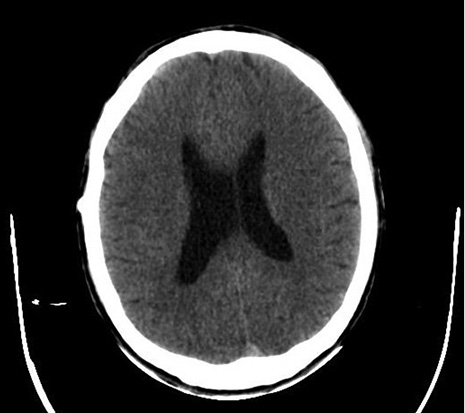

Mujer de 43 años, habitante de la calle, farmacodependiente, con antecedente de Diabetes mellitus tipo 2 en manejo con antidiabéticos orales, quien es encontrada en vía pública inconsciente, es trasladada a centro asistencial donde ingresa en malas condiciones generales, taquicárdica, hipertensa, desaturada, con abundante movilización de secreciones en vía aérea y con escala de glasgow 4/15. Se realiza tomografía computarizada (TC) que no muestra focos isquémicos o hemorrágicos agudos, ni otras alteraciones.

Figura 1. Tomografía cerebral. Fuente: historia clínica de la paciente

Es valorada por neurocirugía quien conceptúa que la TC muestra hidrocefalia por lo que se lleva a derivación externa. Figura 1.